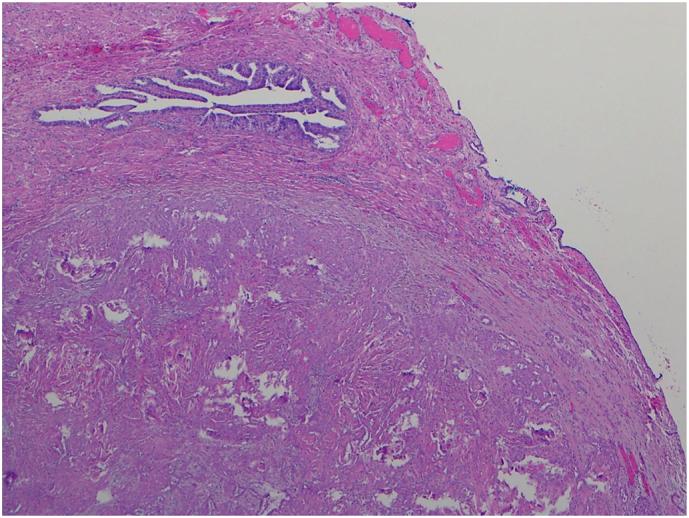

•Incidental finding of a fallopian tube lesion at the time of bilateral salpingectomy•Histopathological appearance not consistent with mucinous or serous carcinoma, appearance of mesothelioma•Very rare known primary neoplasm of tubal mesothelium, favours an indolent course•Recommendation for prophylactic hysterectomy and bilateral oophorectomy•If nil further spread, generally nil further treatment is required.

•双侧输卵管切除术时偶然发现输卵管病变

•组织病理学表现不符合黏液性或浆液性癌,符合间皮瘤表现